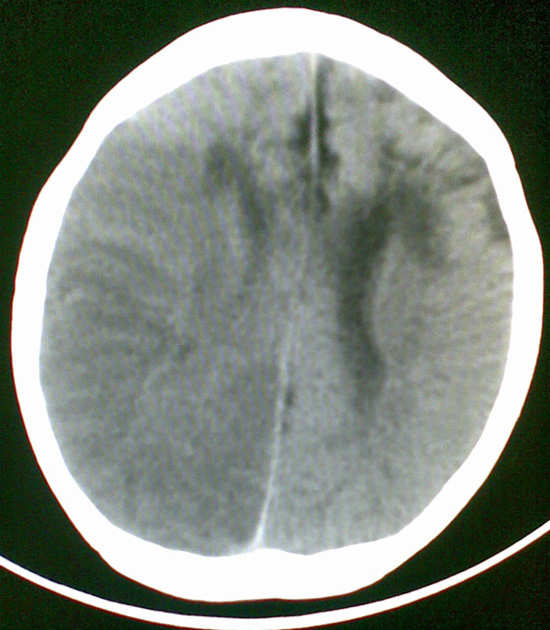

男4岁,反复抽搐多年,今早再次大抽搐,伴昏迷

考虑---右侧大脑半球脑梗死

右侧大脑半球密度减低,脑组织肿胀,占位?建议增强。

考虑脑梗塞. kaolv 血管病变---烟雾病可能

1)右侧大脑半球大面积脑梗塞。2)双侧额叶脑软化灶。3)脑萎缩。

建议:必要时行dsa检查排除烟雾病可能。

右侧半球梗塞,多发软化灶,考虑血管畸形继发,进一步检查。

右侧大脑半球大面积脑梗塞。双侧额叶脑软化灶。考虑血管畸形继发,建议进一步检查。

1右侧大面积脑梗死2左侧额颞部软化灶。